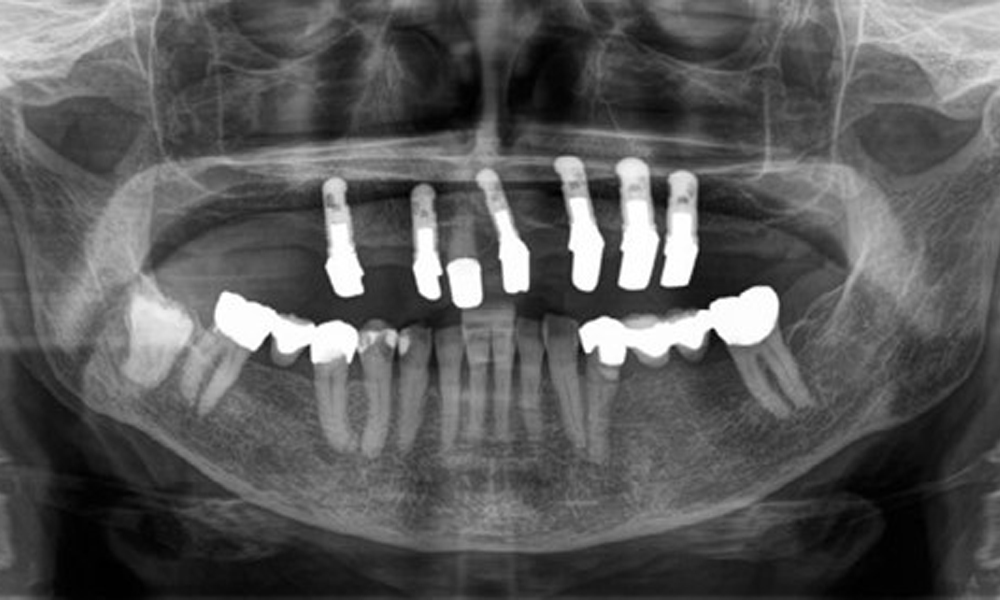

Radiological findings

The radiological findings show partially edentulous dentition with maxillary implants for teeth 15, 13, 21, 23, 24, 25 and a telescopic crown on tooth 11. Adequate mandibular bridges spanning 37 to 34 and 45 to 47 are present. 48 is impacted. There are suspected secondary caries distally on 43 and mesially on 44. 44 is restored with a non-radiopaque cavity lining. There is generalised horizontal bone loss of approx. 10% to 30% and localised vertical bone loss affecting teeth 22 and 42 (Fig. 5).